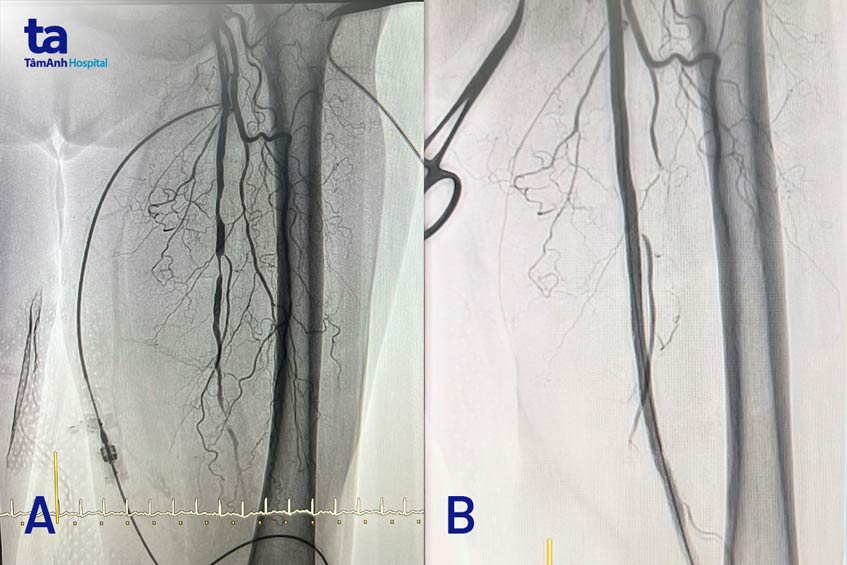

Bác sĩ Dũng cho biết, hình ảnh phim chụp cho thấy cả hai động mạch đùi trái – phải của bà Vân đều bị tắc hẹp, trong đó bên trái tắc hoàn toàn, máu gần như không xuống tới chân. Chính vì không có máu nuôi nên vết thương của bà mới bị nhiễm trùng, các mô hoại tử chuyển màu tím. Các bác sĩ quyết định phẫu thuật ngay để cứu chân trái trước nguy cơ cắt chân.

Trước khi đặt stent tái thông mạch máu, các bác sĩ cẩn trọng loại bỏ từng mảng xơ vữa gây bít tắc mạch máu. Kết quả chụp kiểm tra sau thủ thuật cho thấy dòng máu động mạch đùi nông thông tốt, các nhánh động mạch bàng hệ (phát triển nhiều do tình trạng hẹp tắc) giảm rõ rệt ngay sau khi các tổn thương hẹp tắc đã được xử lý. Bệnh nhân giữ được chân, tránh nguy cơ phải cắt cụt.